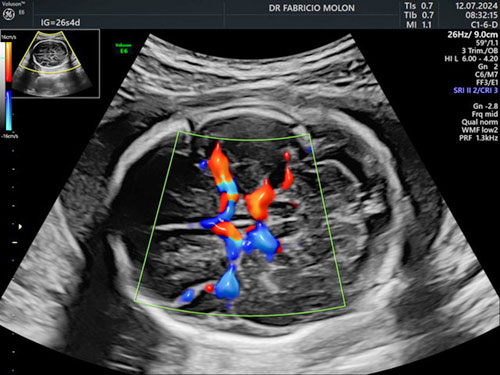

Dopplerfluxometria obstétrica

Um exame focado na análise da circulação da mãe e do bebê.

Algumas questões que vamos avaliar neste exame:

• A saúde da placenta;

• Indícios pré-eclâmpsia;

• Doença hipertensiva;

• Rastreamento de anemia fetal;

• Fluxo das artérias uterinas;

• Crescimento e movimentação fetal.